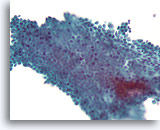

Atypische ductale hyperplasie, Borst FNA, Celblok.

Dit plaatje van de naaldspoeling van de patiënt in afbeelding 15 toont een uniforme populatie van vrijelijk stratificerende ductale cellen met een uniforme spreiding van kernen, afwezigheid van een stromingspatroon en de aanwezigheid van uniformere ronde ruimten in het kleinere fragment.

Atypische ductale hyperplasie, Borst FNA, Celblok.

Dit plaatje van de naaldspoeling van de patiënt in afbeelding 15 toont een uniforme populatie van vrijelijk stratificerende ductale cellen met een uniforme spreiding van kernen, afwezigheid van een stromingspatroon en de aanwezigheid van uniformere ronde ruimten in het kleinere fragment.

Atypische ductale hyperplasie, Borst FNA, Celblok.

Let op de gelijkvormigheid van de cellen (dit duidt op een afwezigheid van myoepitheliale cellen) en de uniforme spreiding van cellen zonder gedeelde polariteit.

Atypische ductale hyperplasie, Borst FNA, Celblok.

Let op de gelijkvormigheid van de cellen (dit duidt op een afwezigheid van myoepitheliale cellen) en de uniforme spreiding van cellen zonder gedeelde polariteit.